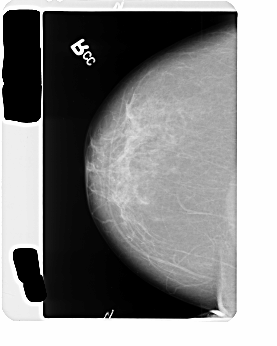

B_3476_1.LEFT_CC

LEFT_CC LINES 4504 PIXELS_PER_LINE 2912 BITS_PER_PIXEL 12 RESOLUTION 50 OVERLAY